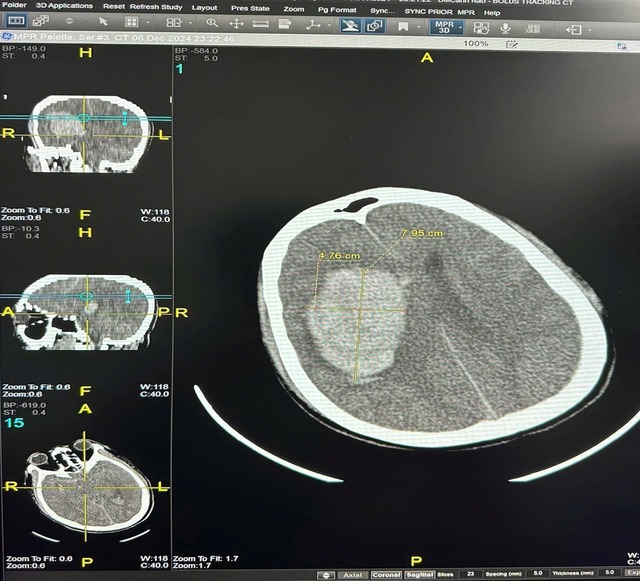

Trường hợp đầu tiên, đêm ngày 6/12/2024 khi bắt đầu đợt không khí lạnh gần đây nhất, một bệnh nhân nam Đ.V.Đ (45 tuổi, ở Hà Nội) không có tiền sử bệnh lý, đã phải cấp cứu trong tình trạng hôn mê sau khi tắm khuya. Kết quả chẩn đoán cho thấy xuất huyết não với khối máu 90 cm³, và bệnh nhân buộc phải phẫu thuật mở sọ để giải ép áp lực não, hiện tại bệnh nhân vẫn phải điều trị tích cực, duy trì thở máy, tiên lượng rất nặng.